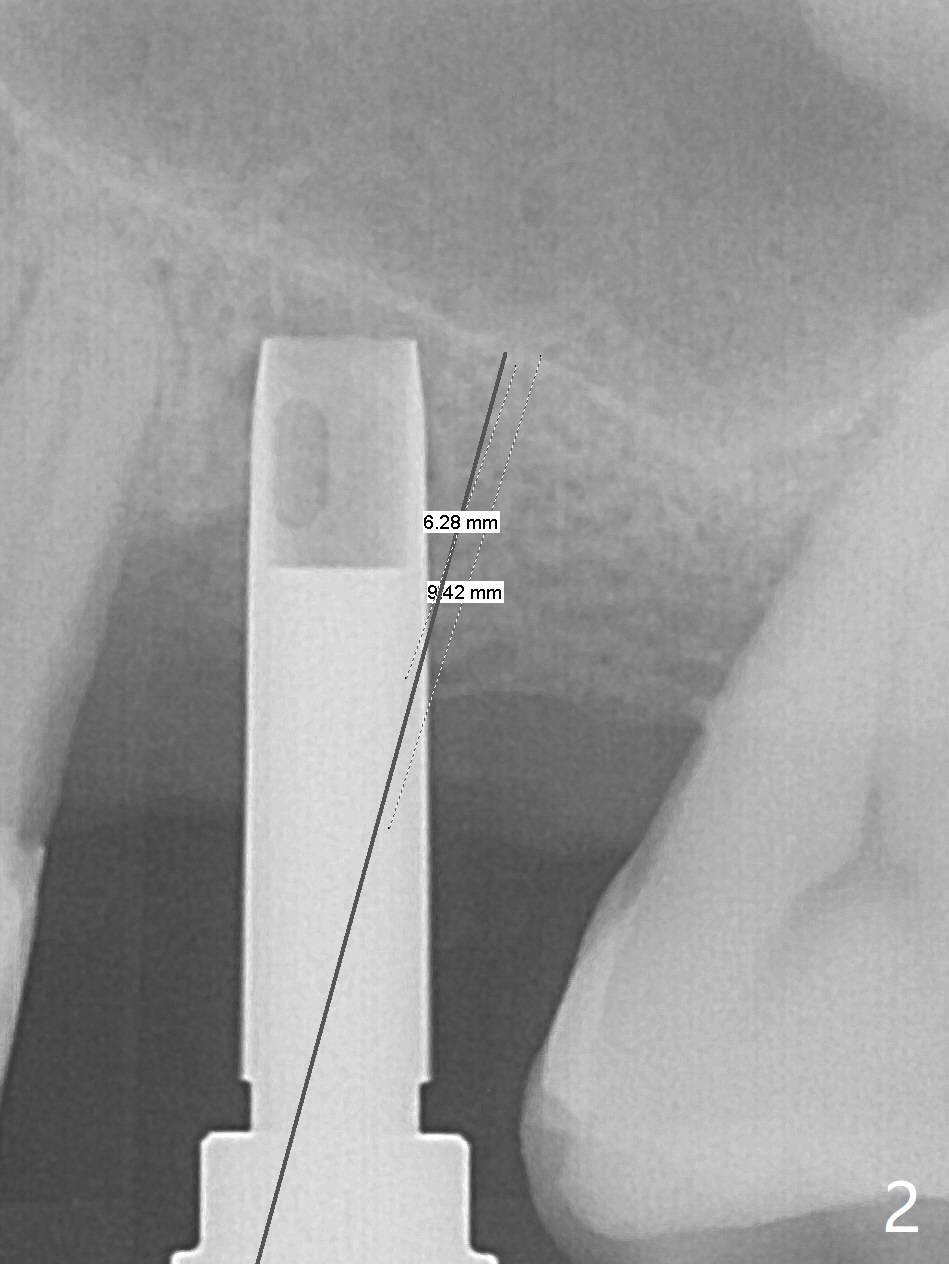

Trajectory of sinus lift without guide at #14 is off (Fig.1 (Magic Sinus Lifter (L) for 9 mm (gingival level)) and needs to be corrected (Fig.2 long line) by re-using 4.8 mm Magic Drill. Following placement of PRF membrane and Demineralized Cortical Allograft (.125-.850 mm) for sinus lift (Fig.3 black dashed line), a 4x10 mm dummy implant is placed with off trajectory. The latter will be fixed by using Lindmann bur to remove the bone distal (Fig.4). The result is less satisfactory with placement of 4.5x10 mm dummy implant (Fig.5). It appears necessary to initiate a new osteotomy (Fig.6 long black line). In fact the result is appealing (Fig.7). The final implant (5x7.3 mm) seems to be placed ideally shown by PA (Fig.8) and BW (Fig.9). Immediately postop CT demonstrates distal defect (Fig.10 *;3-D) and supracrestal placement palatal (Fig.11 P; coronal section). More allograft is then placed in these 2 areas. In all, it is difficult to establish a correct osteotomy without guide. The patient return for uncover 3.5 months postop, although there is a small hole in the middle of the incision (Fig.12). The crown/abutment becomes loose less than 1 month post cementation when the patient chews something tough. It is more related to the unfavorable implant/crown ratio. It is loose again 2 months later. Screw driver is buried inside the abutment with plumber tape. When it is loose for the 3rd time 13 months post cementation, the existing screw driver with a created slot (for retention) is buried without plumber tape after retorque at 35 Ncm (Fig.13). A tissue-level implant should have been used.